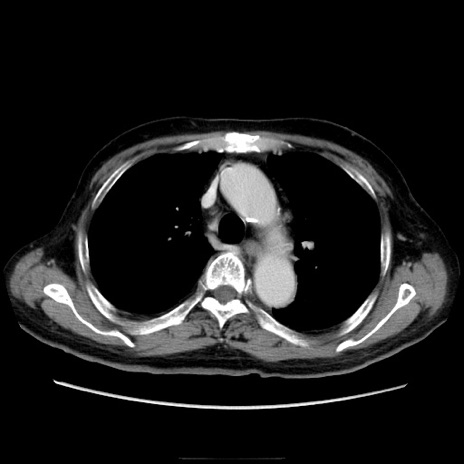

症例21(横断像)

【症例】70歳代男性

【主訴】腹痛

【現病歴】肝硬変・肝細胞癌にてかかりつけの方。約9時間前に食後より腹痛出現。症状が徐々に増悪し、嘔吐出現したため来院。

【既往歴】肝硬変、肝細胞癌(RFA、TACE後)

【身体所見】意識清明、表情苦悶様、BT 36℃、BP 129/78mmHg、P 88bpm、SpO2 97%(RA)、右上腹部から心窩部にかけて圧痛あり、反跳痛なし、筋性防御あり。

【データ】WBC 5800、CRP 0.16